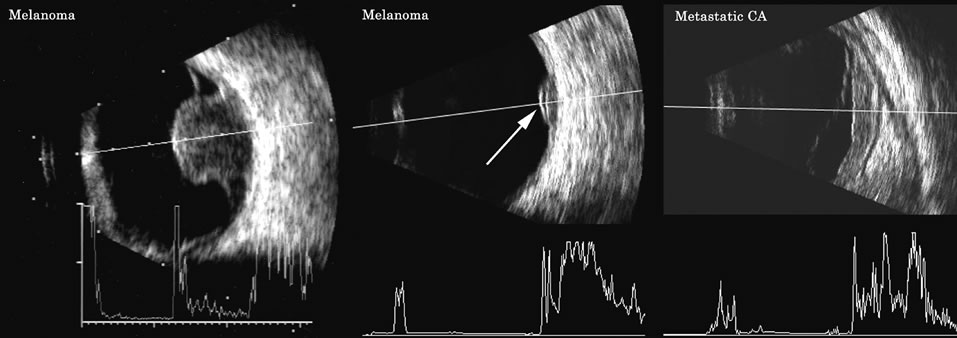

Malignant melanoma varies in its ultrasound presentation from a relatively homogeneous to heterogenous lesion on B-scan. The typical uveal melanoma absorbs sound so that the posterior section is relatively less echoic than the anterior aspect, producing a gradually decreasing amplitude, often to baseline on the A-scan (Fig. 21).

Fig. 21. An ocular tumor at the posterior pole showing the smooth convex border and solid internal reflectants typical of a melanoma.

Melanomas also have varying amounts of melanin, a highly acoustically reflective pigment. As noted, melanomas characteristically show high reflectivity anteriorly, with decreasing reflectance as the sound traverses the tissue. This produces the decreasing amplitude posteriorly in the tumor seen on A-scan and gray-scale B-scan. This effect often enhances the anterior scleral boundary. The posterior tumor border is thus measured as the first “rising” echo from the tumor decline, and it is most easily seen and accurately identified on B-scan.27

Metastatic carcinoma is more heterogeneous, producing a more uniform A-scan amplitude of roughly 50% to 80% of the “scleral” echo amplitude (see below) behind the tumor (Fig. 22). Hemangioma is a very highly reflective tumor with high amplitude all the way through the tumor of 80% to 100% of scleral echo amplitude (Fig. 23).

Fig. 22. Some hemangiomas and metastatic carcinomas may simulate a melanoma. They are differentiated on the basis of a very high amplitude internal echo complex for the hemangioma, a moderately low but sustained echo pattern for the metastasis, and an A-scan with decreasing reflectance as the tumor thickness is traversed. In the center scan of a melanoma, note the double anterior layer caused by edema fluid underlying the crest of the melanoma (arrow).

The differentiation of tumor tissues is made possible by differences in cellular organization and concentration.29 Acoustically, these are termed as differences in backscattering properties.30–32 A homogeneous solid tissue, such as the lens or the optic nerve, may present few or no echogenic discontinuities and thus appear anechoic and cyst-like. (An echogenic discontinuity is technically an acoustic impedance mismatch in which the acoustic impedance is the product of the density and the speed of sound in each tissue.) A fluid–smooth tissue boundary has a high mismatch or discontinuity and thus produces a high-amplitude echo. A hemangioma with alternating blood- and tissue-lined sacs thus produces a solid-appearing tissue with high-amplitude echoes seen at all depths of the tissue. A metastatic tumor is nearly always a very heterogeneous tissue with randomly organized clumps of similar cells bounded by strands of vessels, necrotic areas, and connective tissue, thus producing a pattern of moderately high-amplitude sustained echoes.